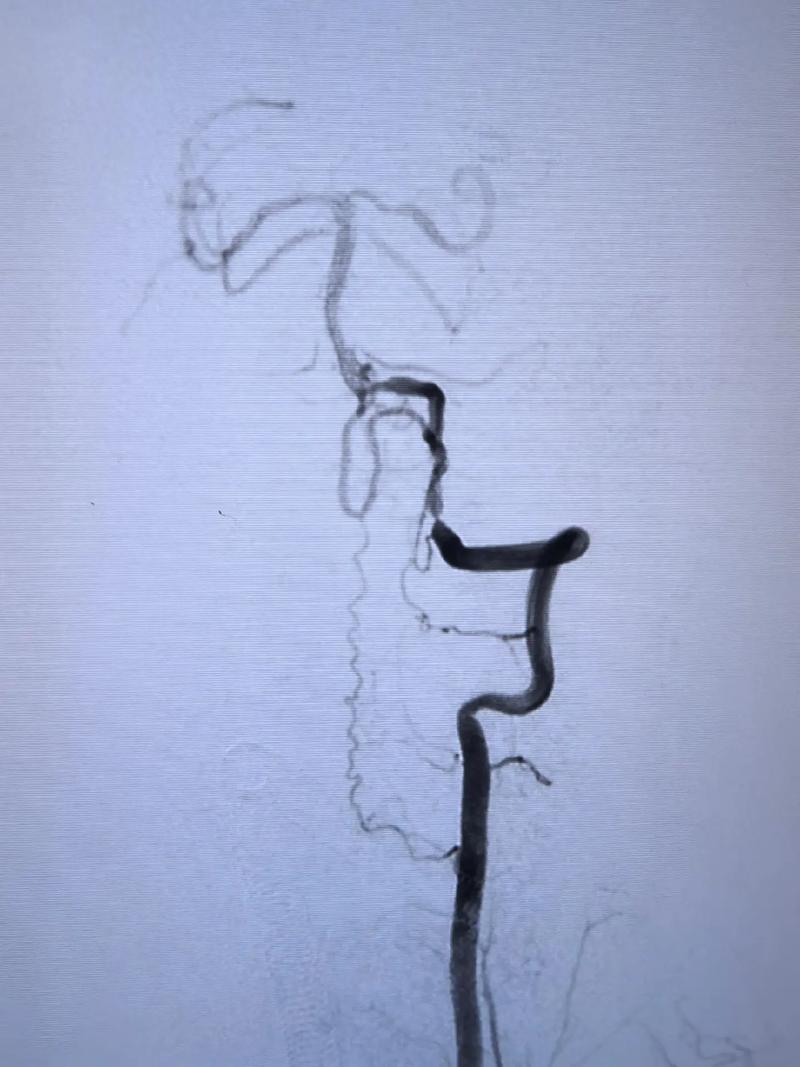

- 影像学检查:通过CTA(CT血管造影)、MRA(磁共振血管造影)或DSA(全脑血管造影,金标准)精确评估狭窄部位、程度、长度、斑块性质(软斑还是硬钙化斑)、血管迂曲程度等。